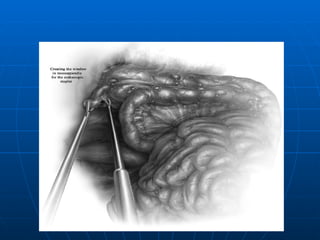

TRATAMIENTO LAPAROSCOPICO Excelente Iluminación y exposición del campo operatorio Disminución de Complicaciones Mayor costo (equipos- anestesia general) Mayor tiempo Operatorio ( 3 Trócares umbilical,suprapúbico (10mm y fosa iliaca izquierda 5mm). En todos los grupos cuando el Apéndice es normal  no se extrae (no así en las convencionales)

TRATAMIENTO LAPAROSCOPICO ExcelenteIluminación y exposición del campo operatorio Disminución de Complicaciones Mayor costo (equipos- anestesia general) Mayor tiempo Operatorio ( 3 Trócares umbilical,suprapúbico (10mm y fosa iliaca izquierda 5mm). En todos los grupos cuando el Apéndice es normal no se extrae (no así en las convencionales)